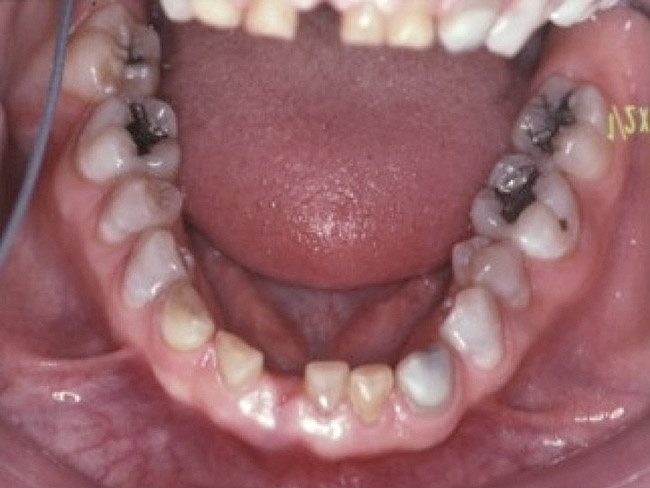

Loss of vertical dimension can be assessed through patient examination intraorally, extraorally, and functionally. Missing teeth and/or teeth worn from clenching or bruxing are the most common intraoral signs of a decreased VDO. Congenitally missing teeth can result in loss of vertical dimension with possible implications of compromised comfort, speech, and chewing (Figure 6 through Figure 8).

Figure 6. The patient is congenitally missing the maxillary lateral incisors and canines and all lower incisors and canines, causing concerns about esthetics. The maxillary laterals and canines and mandibular canines have been bonded with composite.

Figure 6

Figure 7. The mandibular incisors are loose, and No. 25 has recently been lost.

Figure 7

Figure 8. The lower one third of face seems shortened and the upper lip is not well supported and appears thin.

Figure 8